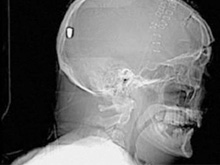

Фото новостиВ Британии у пациента, который поступил в клинику с подозрением на инсульт, врачи обнаружили пулю в голове. Но остается неизвестным, как мужчина получил ранение.

Рентгеновские снимки головы показали, что в полости черепа находится инородный предмет. Мужчине сделали томографию головы, и врачи установили, что этим предметом является пуля.

Эксперты по баллистике, изучив снимки пациента, пришли к выводу, что пуля, застрявшая в затылочной области, могла попасть туда через глаз. Но мужчина не помнит, что именно с ним произошло.

Врачи попытались удалить пулю, однако это оказалось невозможным из-за ее положения по отношению к окружающим структурам. Пациент остается в больнице, а его состояние расценивается как стабильное.